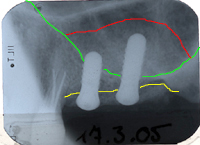

Da nicht mehr als 3 bis 4 mm ortsständiger Knochen vorhanden war, musste zuerst ein Sinuslift gemacht werden, bevor eine neue Brücke auf zwei Implantaten gesetzt werden konnte. Das Resultat des Sinuslifts und die gesetzten Implantate sind in Abb. 2 zu erkennen.